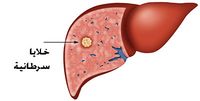

سرطان الكبد

مقالة مفصلة: سرطان الكبد

مقالة مفصلة: سرطان الكبد

| سرطان الكبد | ||

| معدل الانتشار | 618.700 (2015)[7] | |

| معدل البقاء 5 سنوات | ~ 18% (الولايات المتحدة)[10] | |

| حالات الوفاة | 810.500 (2015)[6] | |

| عوامل الخطورة | أكثر من 50% من المصابين بسرطان الكبد الأولي مصابون، أيضاً، بتليف الكبد. وكذلك الأشخاص المصابون بداء ترسب الأصبغة الدموية الوراثي، معرضون بدرجة كبيرة للإصابة بسرطان الكبد.[18] | |

| العلامات المنذرة | أكثر الأعراض شيوعاً، وغالباً ما يكون أولها، هو الألم في المراق الأيمن من البطن، سببه تمطط محفظة الكبد الغنية بالتعصيب، أو ألم في الكتف الأيمن سببه التخريش العصبي للحجاب الحاجز، مما يسبب ألماً منتشراً، وانتفاخ البطن. ويحدث نقص الوزن في نحو 25% من الحالات. وينجم اليرقان عن انسداد القنوات الصفراوية، أما الإقياءات الدموية فهي من الأعراض الأقل شيوعاً. | |

| الكشف والتشخيص | من غير المتبع إجراء فحوصات التصوير بالأشعة بشكل جارف لجميع المرضى من أجل الكشف المبكر عن سرطان الكبد الأولي، ولكن من الممكن فحص إمكانية إجراء هذه الفحوصات للأشخاص الأكثر عرضة للإصابة، بدرجة مرتفعة. وبالرغم من هذا، لم تستطع الأبحاث أن تحدد ما إذا كان التصوير بالأشعة ملائما وناجعا لجميع المرضى. من أجل تشخيص سرطان الكبد، ينبغي أولا نفي (استبعاد) وجود أمراض أخرى قد تكون لها الأعراض ذاتها. | |

| العلاج | أنواع سرطان الكبد هي من بين الأمراض التي من الصعب معالجتها. في حالات قليلة، يتم اكتشاف السرطان الأولي في الكبد في مرحلة مبكرة - المرحلة التي تكون فرص معالجته جيدة. كذلك، تصعب معالجة سرطان الكبد الثانوي أو نقائل سرطان آخر قد انتشرت وانتقلت إلى الكبد، وذلك لأن السرطان في هذه الحالة يكون قد انتشر وتفشى.